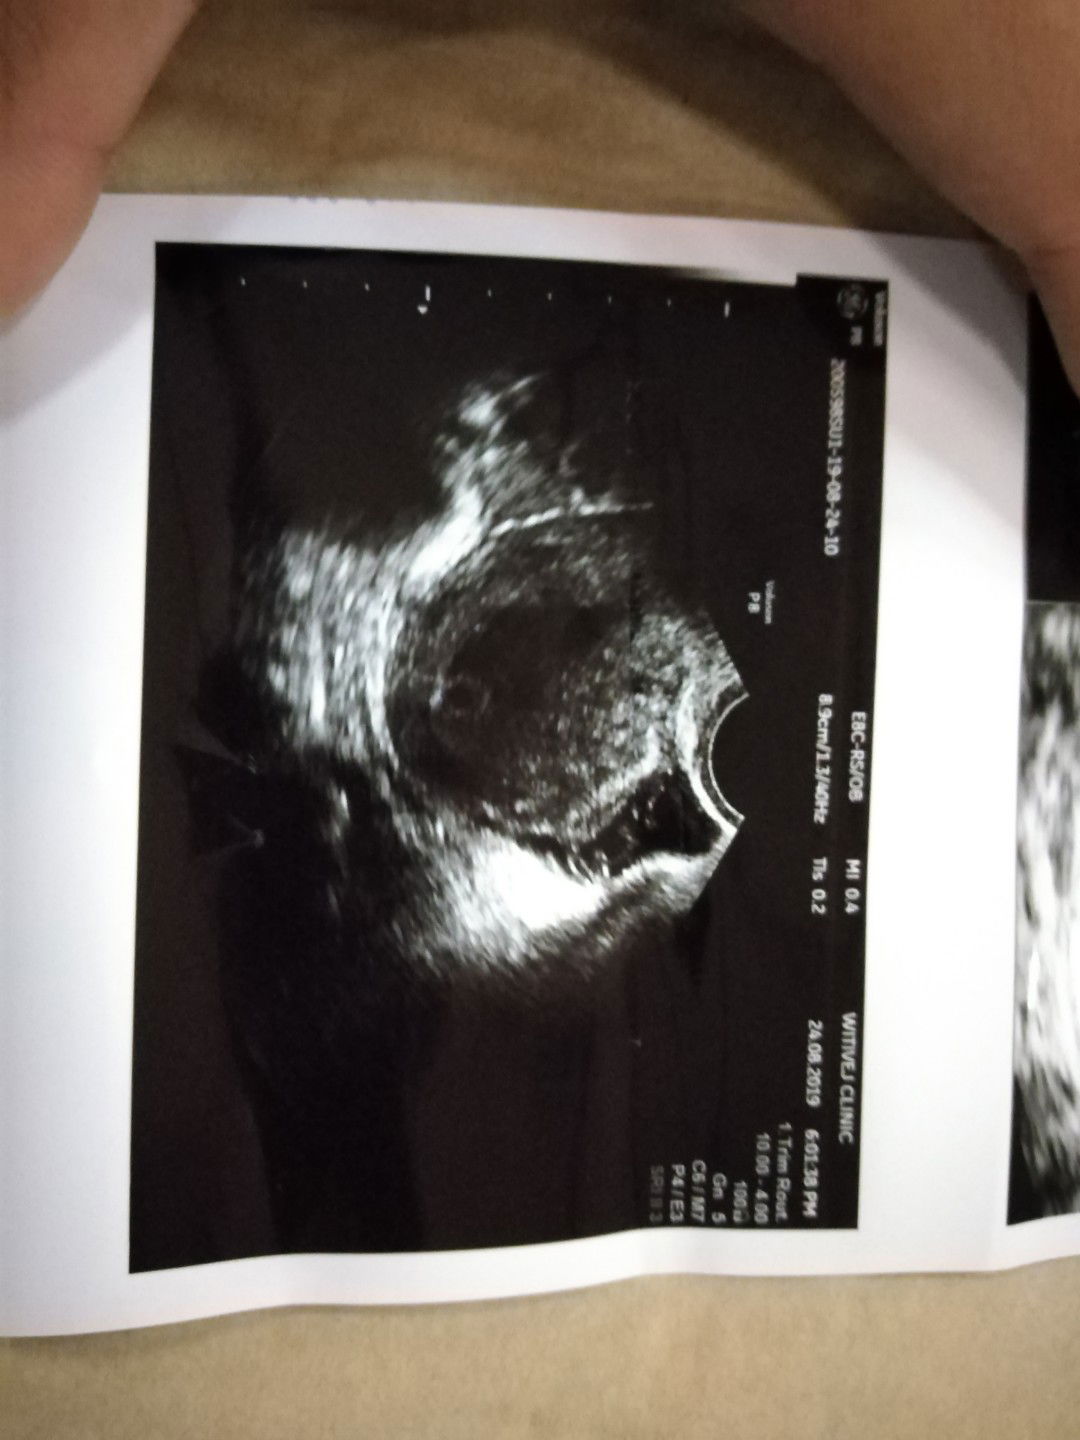

ภาพอัลตร้าซาว6วีค

รบกวนแม่ๆช่วยดูภาพอัลตร้าซาวหน่อยค่ะ 6 วีค คุนแม่เป็นยังไงกันบ้างคั